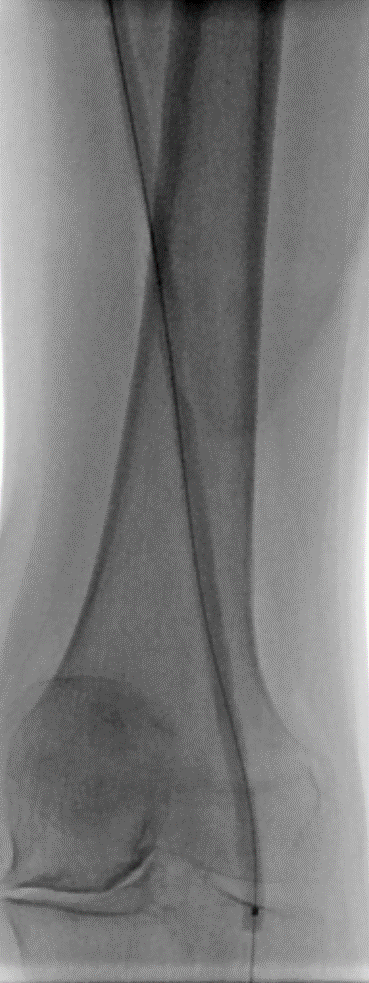

★ Case 6

Severecalcification

★ Case 7

chronicthrombosis

★ Case 8

proximal hard fibrosis cap in SFA